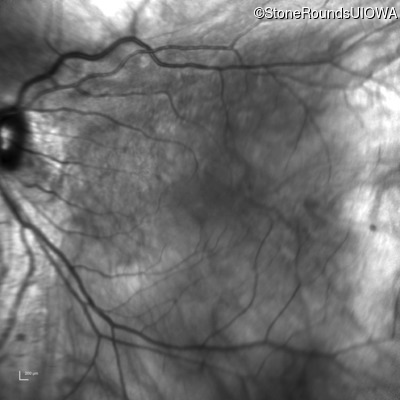

Infrared Fundus Photograph - Left - 20/25 +2

Exemplar